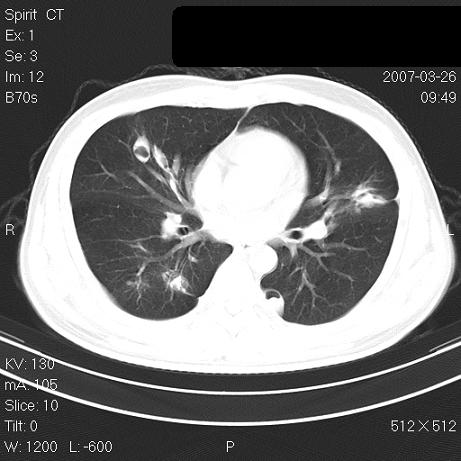

标题: CT7171B:补充治疗后2周复查 [打印本页]

标题: CT7171B:补充治疗后2周复查

治疗后2周复查,请讨论

结合以前的ct片,还是考虑肺挫伤,吸收多了。

支持:创伤性湿肺。现肺挫裂伤(出血 积气)大部分吸收。建议继续治疗!

结合以前的ct片,支持创伤性湿肺。现大部分吸收。

支持:创伤性湿肺、肺挫裂伤。现肺挫裂伤(出血、渗出、液气腔)大部分吸收。建议继续治疗!

支持:创伤性湿肺、肺挫裂伤。现肺挫裂伤(出血、渗出、液气腔)大部分吸收.

结合老片支持创伤性湿肺、肺挫裂伤。

经治疗后病灶明显吸收,考虑创伤性湿肺、肺挫裂伤